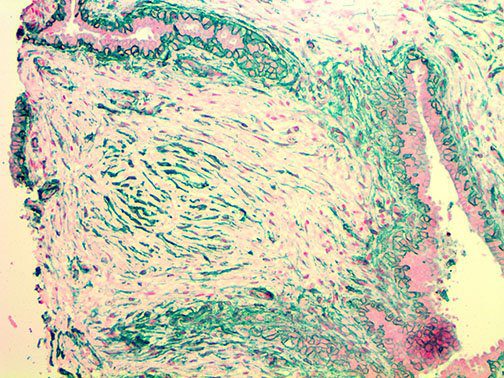

This activation induces inflammatory monocytes to highly express IL-6, starting a localized and then systemic cascade effect that results in hyperproduction of IL-6, which accelerates the inflammatory process. Because IL-6 also increases vascular permeability, excessive levels cause blood vessels to become very leaky. This, along with clotting factors released from vascular endothelial cells, stimulates the coagulation cascade, resulting in microthrombosis (tiny clots), which leads to ischemia and tissue death of the kidney, intestines, heart, liver, brain and extremities.